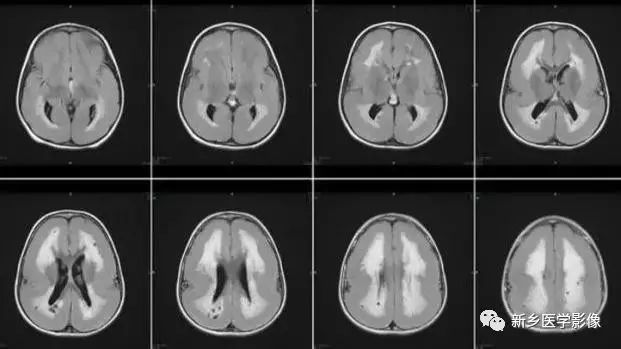

5.脑室周围白质软化症

主要与缺血缺氧及感染有关.常见于早产儿.是造成早产儿脑瘫的主要原因。由于脑室周围白质的血供分别来自脑室区和远脑室区的终动脉。未成熟儿终动脉深穿支的侧支循环尚未建立,而胚胎晚期脑室周围白质对缺血缺氧敏感。所以,脑室周围自质软化症多见于早产儿。由于病灶常为双侧性,故双侧侧脑室多同时扩大。脑白质内软化灶在CT扫描时表现为白质内斑片状低密度灶.MR T1加权图呈低信号,T2加权图呈高信号。

6.脑室周围白质软化症

主要与缺血缺氧及感染有关。

常见于早产儿。常见于早产儿的原因与胚胎期脑部损害发生的时间有关,胚胎早中期脑损害主要引发发育畸形,晚期主要引起脑血管改变。

由于脑室周围白质的血供分别来自脑室区和远脑室区的终动脉,未成熟儿终动脉深穿支的侧支循环尚未建立,而胚胎晚期脑室周围白质对缺血缺氧敏感。所以,脑室周围白质软化症多见于早产儿。

由于侧脑室周围有软化萎缩,故扩大的侧脑室外缘常不规则,不光整,这种不规则、不光整是本病引起脑室扩大的特征,另外,本病均表现有脑白质量减少及脑白质内斑片状软化病灶,脑白质减少严重时表现为部分区域白质消失,脑皮层与脑室侧缘接近甚至相连。CT表现为斑片状低密度灶。MR T1WI上呈低信号,T2WI呈高信号。